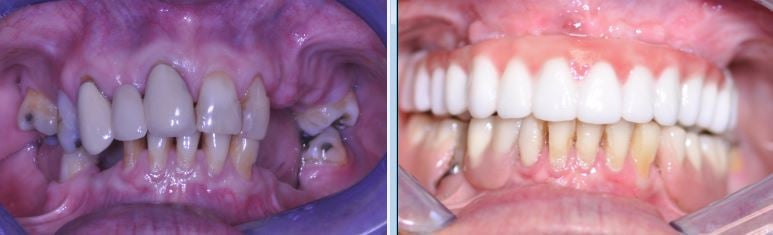

FULL MOUTH RECONSTRUCTION

This is one of the most difficult, so called “multidisciplinary” cases.

Wide spectrum of dental techniques and clinical procedures was used during this complex dental therapy. Among those were the following:

- Neuromuscular Diagnosis and Treatment of TMD-TMJ

- Dental Implants, Bone grafts & Sinus Lifts

- CAD/CAM Digital Restorative Dentistry

- Cosmetic All-ceramic Veneers, Crowns and Dental Bridges

- Teeth Extractions

- Laser Dentistry, Digital X-Rays, Virtual Smile Design

- Bio-mimetic Dentistry

I have been a patient of Dr. Andrews for many years. I am so happy that I found this wonderful dentist. I lost most of my teeth, had problems with TMJ and my bite was off.

My life was greatly affected by my dental problems, I couldn’t chew and was in chronic pain. Dr. Andrews fixed my teeth, placed dental implants and made beautiful set of new dazzling choppers. Literally pain free dentistry, great experience and my life is back on track. Thank you Dr. Andrews